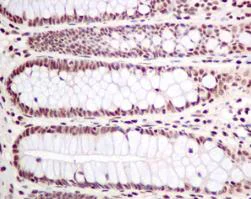

ab155095 staining PLK1 (phospho T210) in Human colon tissue sections by Immunohistochemistry (IHC-P - paraformaldehyde-fixed, paraffin-embedded sections). Tissue was fixed and paraffin-embedded, antigen retrieval was by heat mediation in Tris/EDTA buffer pH9. Samples were incubated with primary antibody (1/500). An undiluted HRP-conjugated  anti-rabbit IgG was used as the secondary antibody. Tissue counterstained with Hematoxylin. PBS was used in the negative control rather than the Primary antibody.

This data was developed using the same antibody clone in a different buffer formulation containing PBS, BSA, glycerol, and sodium azide (ab155095).